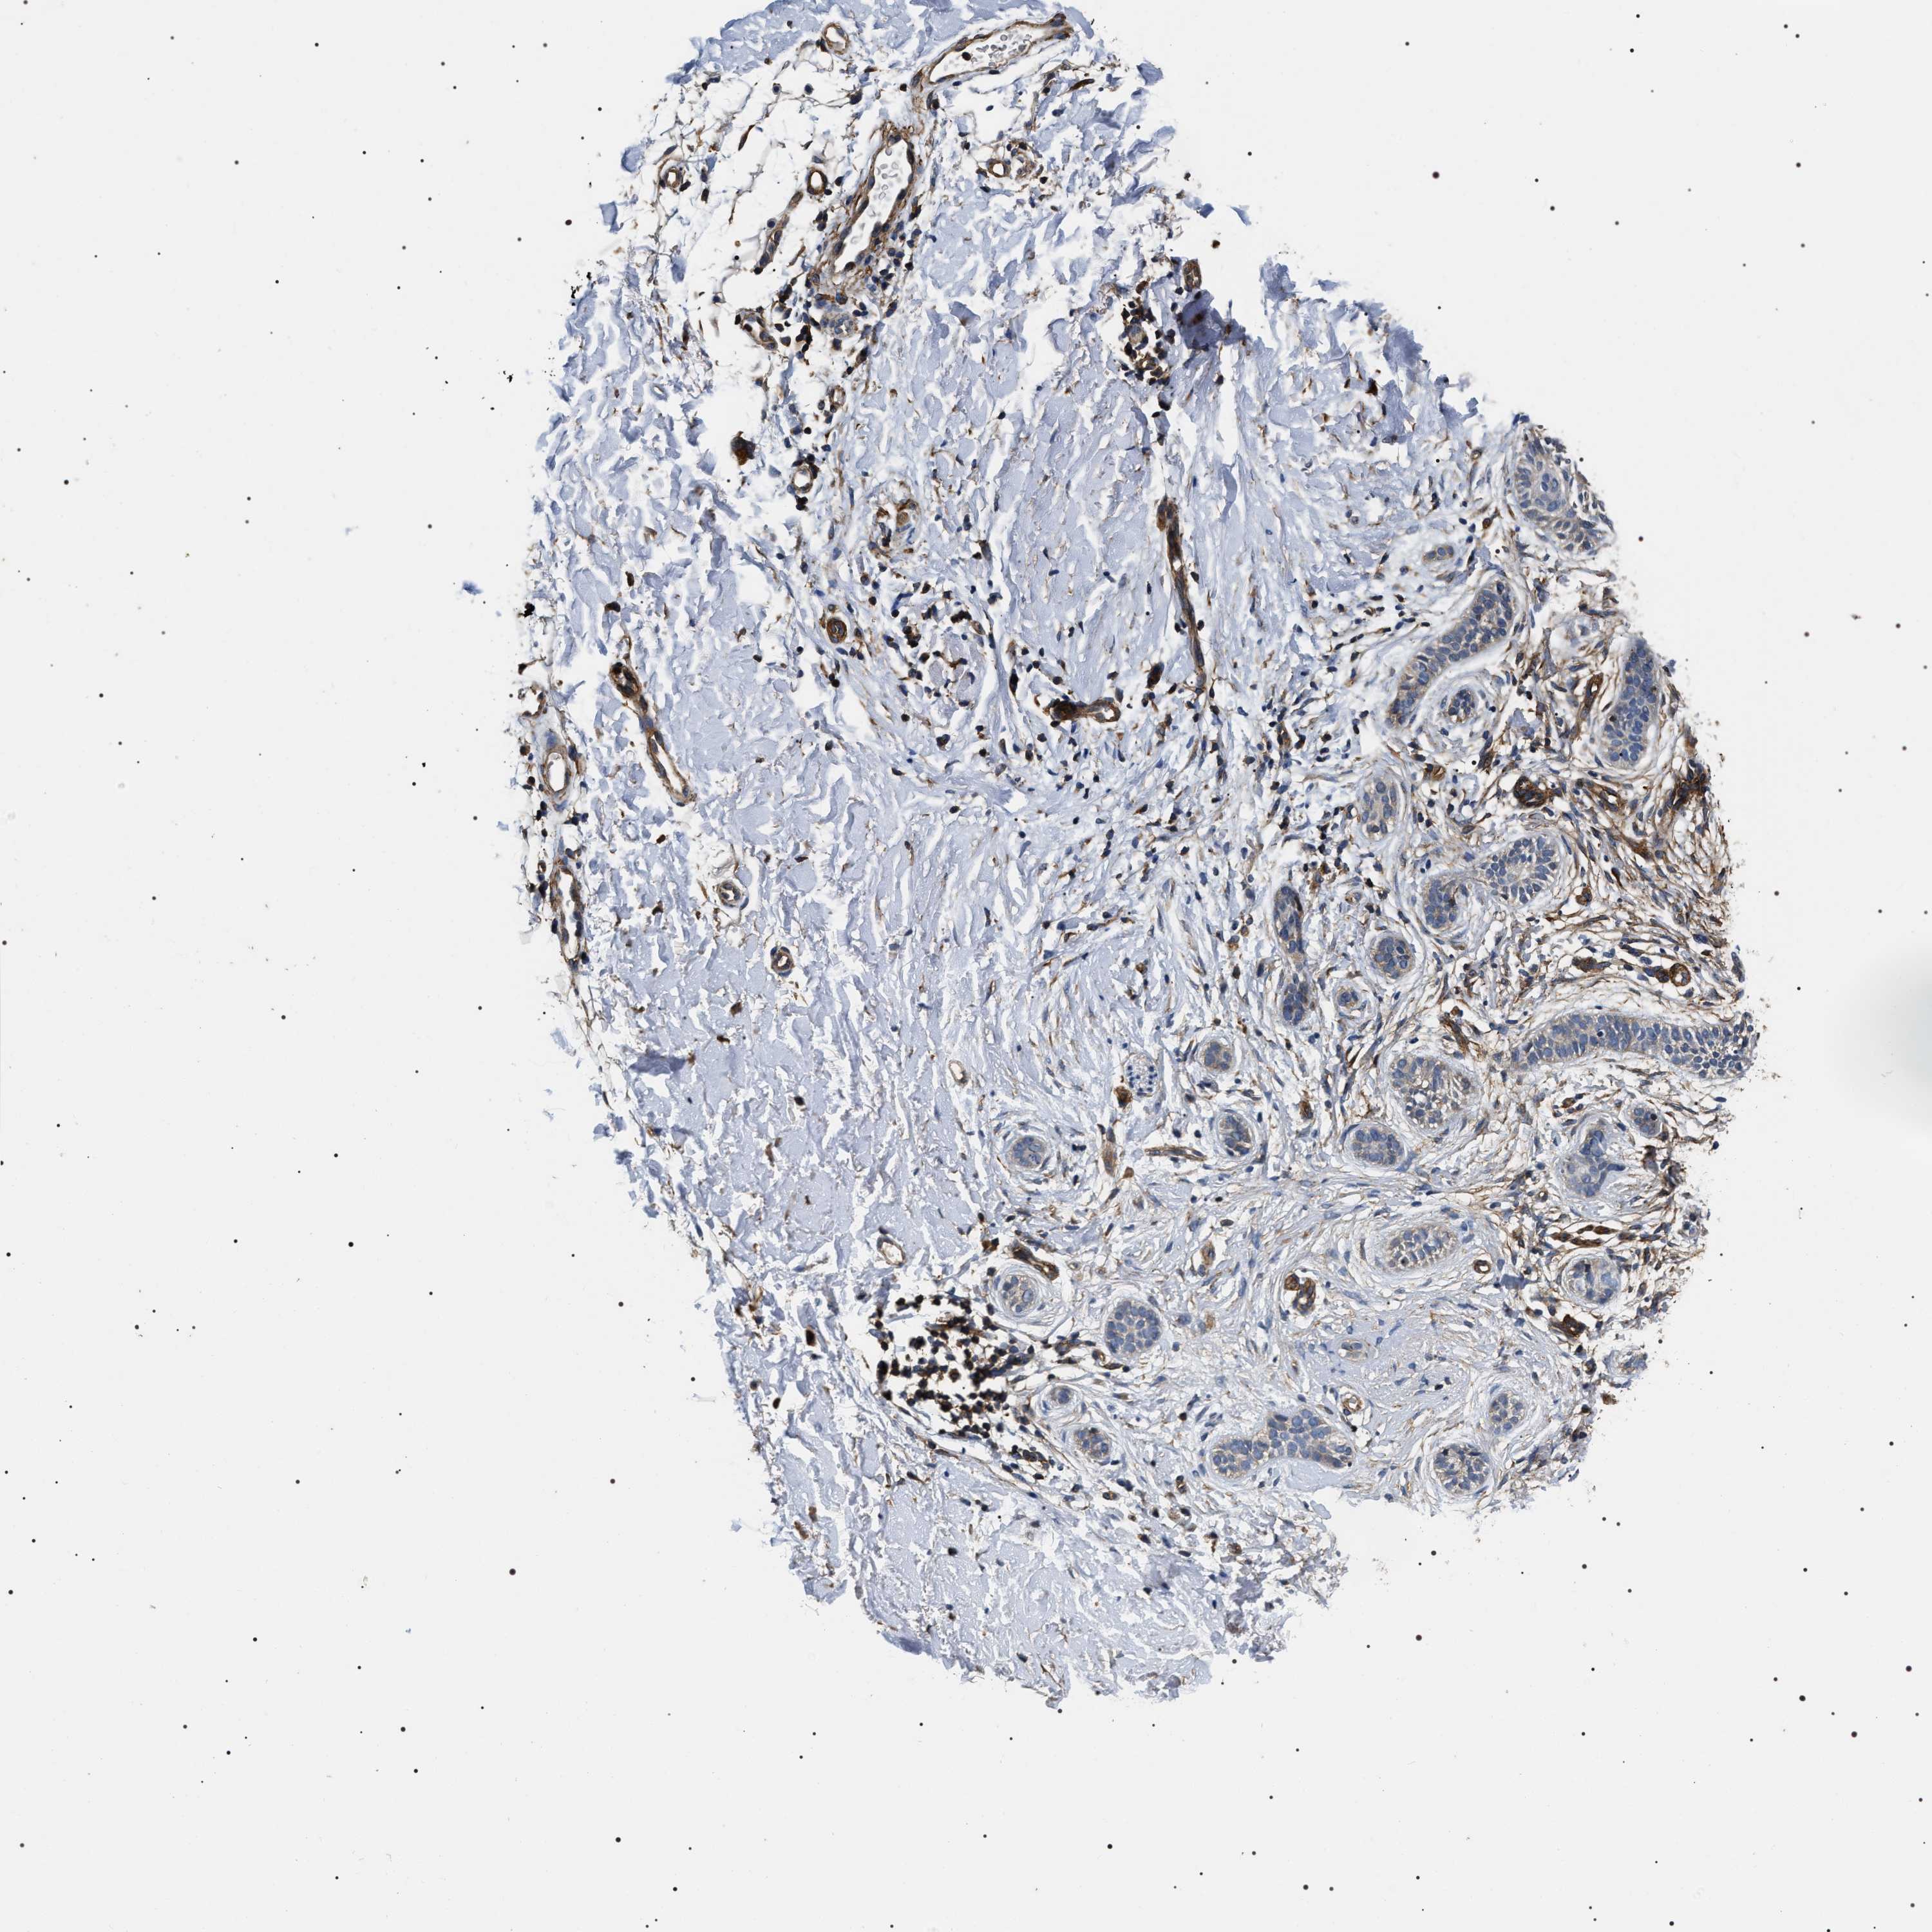

CANCER SKIN CANCER Show tissue menu

Basal cell and squamous cell cancer

SKIN CANCER - Protein expressioni

A mouse-over function shows sample information and annotation data. Click on an image to view it in a full screen mode. Samples can be filtered based on level of antibody staining by selecting one or several of the following categories: high, medium, low and not detected. The assay and annotation is described here.

Each image is clickable and will lead to virtual microscopy that enables deeper exploration of all samples and also displays staining intensity scores, fraction scores and subcellular localization as well as patient and tissue information for each sample.

Antibody HPA020386

Basal cell carcinoma